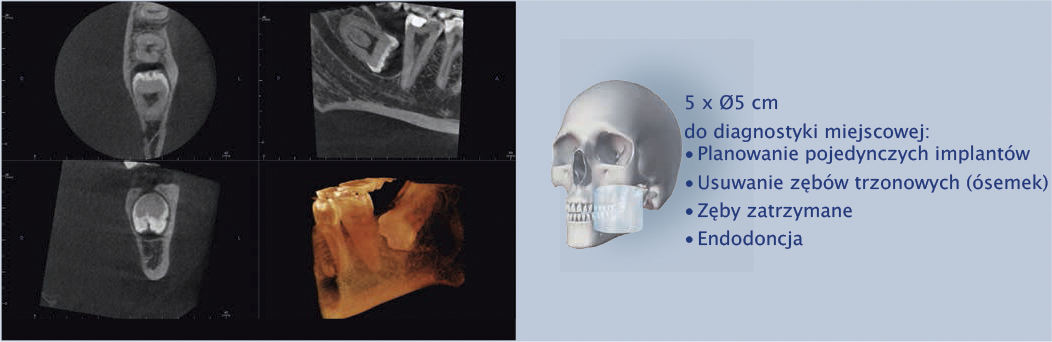

Cztery różne pola obrazowania zapewniają niezawodną diagnostykę 3D w całym obszarze jamy ustnej. Zapewniają one precyzyjne dopasowanie, odpowiednie do wskazań a także uniwersalne możliwości zastosowania w codziennej praktyce – od endodoncji, poprzez implantologię do chirurgii jamy ustnej.